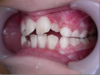

La classe 2 (d'après la classification Ballard): les dents du haut sont trop en avant. Celles du bas sont elles, trop en arrière.

deep bite : les dents du bas sont trop recouvertes par celles du haut.